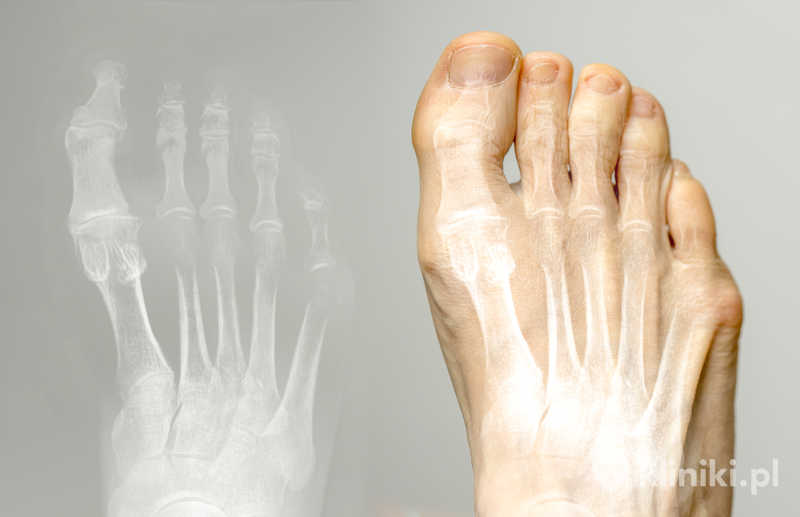

Paluch sztywny to przewlekła choroba zwyrodnieniowa stawu śródstopno-paliczkowego palucha (MTP I), prowadząca do jego zniekształcenia i ograniczenia ruchomości. Najbardziej charakterystycznym objawem jest ból pojawiający się w trakcie chodzenia oraz trudności w zginaniu palucha ku górze.

W wyniku choroby dochodzi do tworzenia się wyrośli kostnych (osteofitów) w obrębie grzbietowej powierzchni stawu, które fizycznie blokują jego ruch. Powierzchnie stawowe ulegają zwyrodnieniu, a przestrzeń stawowa ulega zwężeniu. Wszystko to przekłada się na pogorszenie komfortu chodzenia i znaczne ograniczenie sprawności stopy.

Podstawową różnicą między paluchem sztywnym a haluksem (paluchem koślawym) jest kierunek deformacji i mechanizm choroby. Paluch sztywny to zaburzenie ruchomości stawu bez wyraźnego odchylenia osi palucha, natomiast w haluksie dochodzi do wyraźnego przyśrodkowego przemieszczenia palucha i bocznego przemieszczenia I kości śródstopia. W przypadku palucha sztywnego nie obserwuje się charakterystycznego „wybrzuszenia” po wewnętrznej stronie stopy, typowego dla haluksów. Deformacja dotyczy tu głównie ograniczenia ruchu i tworzenia osteofitów na grzbietowej powierzchni stawu.